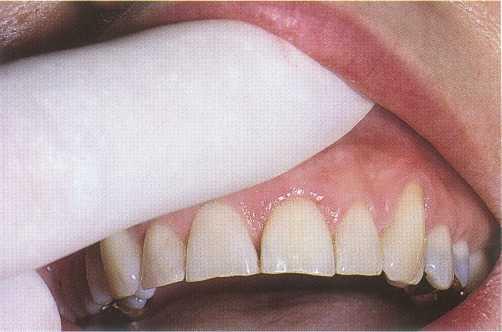

Visual inspection of the soft tissues should include an assessment of color, contour, and consistency. Localized redness, edema, swelling, or a sinus tract can indicate inflammatory disease. Examination of the hard structures may reveal clinical findings such as developmental defects, caries, abrasion, attrition, erosion, defective restorations, fractured cusps, cracked teeth, and tooth discoloration (Figure 1-1).

FIGURE 1-1

A 32-year-old woman presents for treatment of spontaneous pain that keeps her awake at night. She relates a history of orthodontics and a frenectomy as an adolescent, as well as traumatic injury to the maxillary anterior area during a basketball game. Clinical examination reveals normal-appearing soft tissues, scar formation consistent with location of the suture placed after the frenectomy, and discoloration of the maxillary left central incisor, tooth #9.